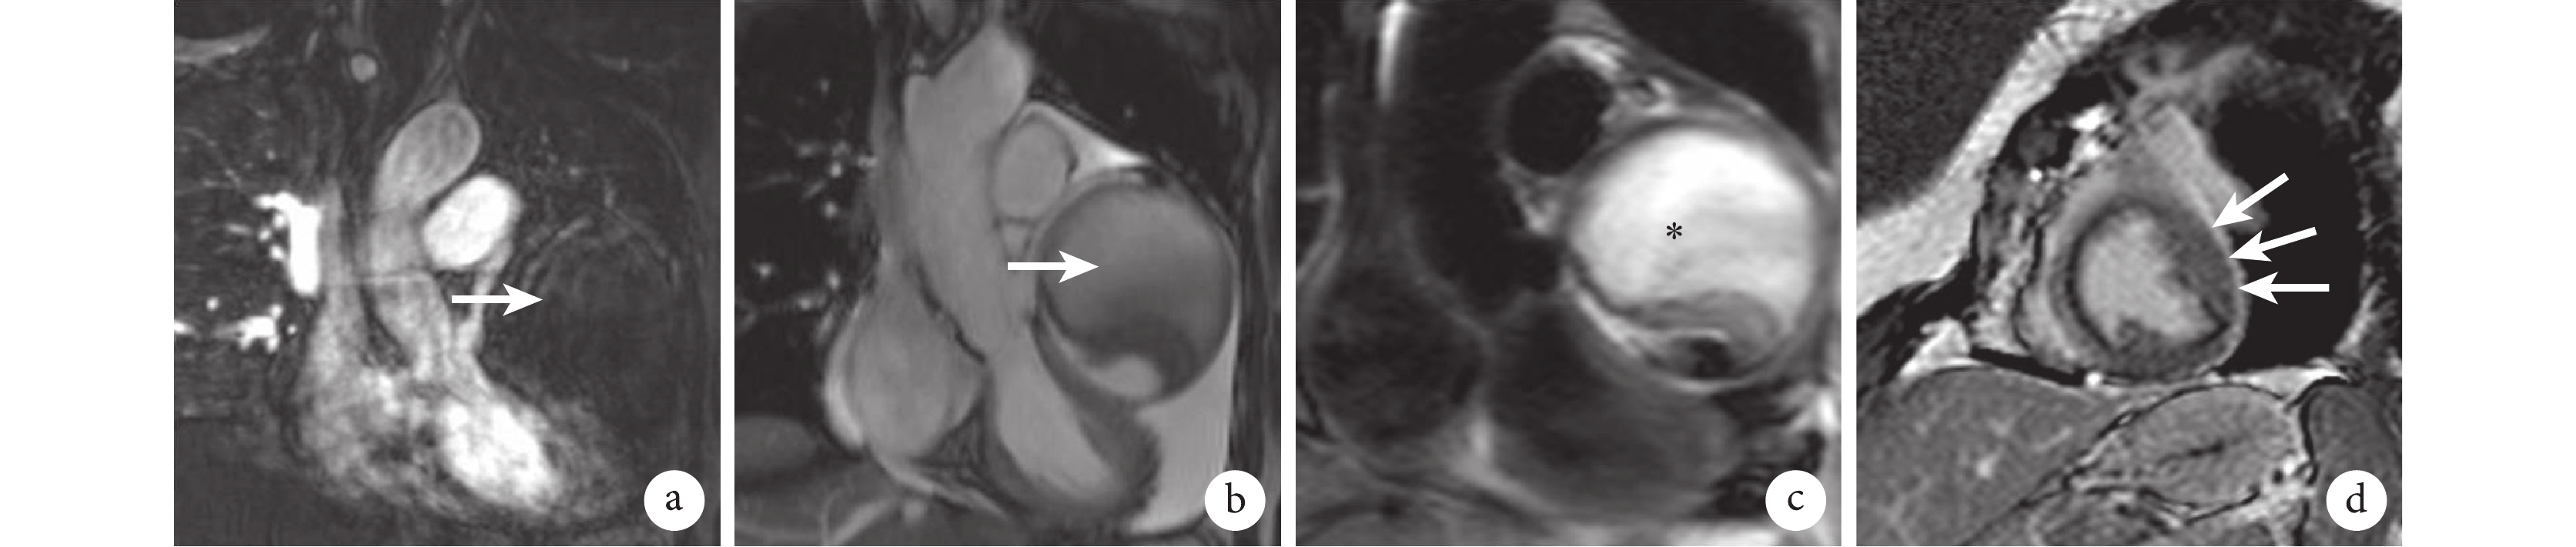

a. 增強掃描顯示左冠狀動脈前降支近段處巨型冠狀動脈瘤形成(白箭);b. T2 加權像顯示左冠狀動脈前降支近段處巨型冠狀動脈瘤形成(白箭);c. 黑血序列顯示瘤內大量陳舊性血栓形成,呈混雜高信號影(*);d. 延遲強化示左心室游離壁少許小片狀強化影(白箭)

輔助檢查:入院后患者行血常規、心肌標志物、凝血常規等各項生化檢查。除纖維蛋白及纖維蛋白原降解產物稍升高(5.3 mg/L;參考值<5 mg/L)、D-二聚體稍增高(1.65 mg/L;參考值<0.55 mg/L)外,血常規及其他生化檢查各指標未見明顯異常;心肌標志物中肌紅蛋白、肌酸激酶同工酶及肌鈣蛋白-T 也均處于正常范圍內。本院冠狀動脈數字減影血管造影(digital subtraction angiography,DSA)檢查(2017 年 12 月 18 日)顯示:① 左冠狀動脈前降支粗大彎曲,遠段顯示不清,似與一造影劑涂染腫塊影連接(圖 1);② 右冠狀動脈圓錐支遠段可見瘺口至肺動脈(圖 2)。本院心臟 MRI 檢查(2017 年 12 月 26 日)顯示:① 左心室旁見混雜信號腫塊影,大小約 8.6 cm×7.2 cm×8.5 cm,左心室受壓,疑為動脈瘤;② 主肺動脈窗內見增粗迂曲血管影;③ 延遲掃描室間隔、左心室前壁及側壁散在點片狀異常強化影,合并缺血性心肌病可能(圖 3);④ 左、右心室功能未見明顯減低;⑤ 心包中量積液。

在本例患者的心臟 MRI 檢查結果中未見左、右心室收縮舒張功能異常,同時通過文獻復習也發現大多數 CAE 不會引起患者死亡,但 CAE 血管內膜的病理性改變及局部血流動力學異常極易使瘤內發生血栓[17]。本例患者左冠狀動脈瘤內合并大量陳舊性血栓,并壓迫左心室,其誘發心肌梗死的風險大大提高,且其心臟 MRI 可觀察到左心室室前壁及側壁局灶性的延遲強化的出現也提示了左心室已出現局灶性心肌缺血,又因合并大量心包積液,導致其癥狀較一般 CAE 患者癥狀明顯。采取積極的手術治療,可有效提高患者生存質量,應作為首選治療方案。